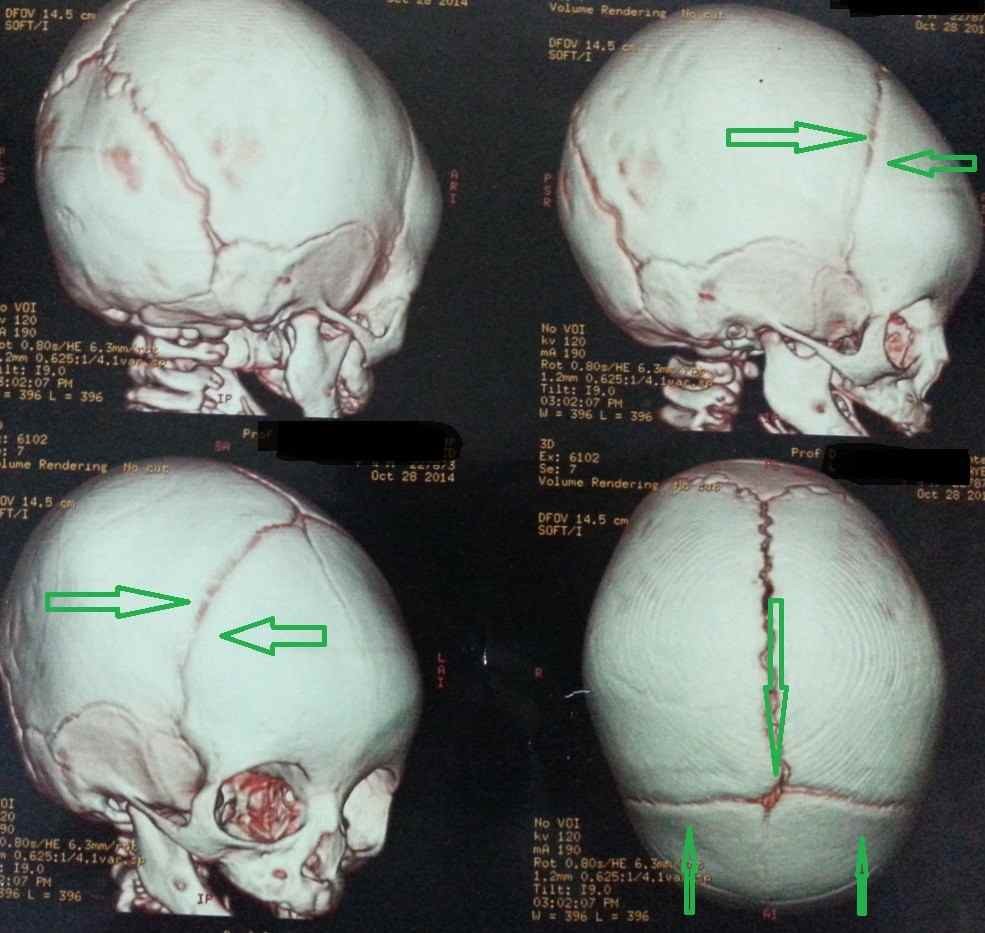

premature closure of the coronal sutures with a small forehead in a 4-month-old girl